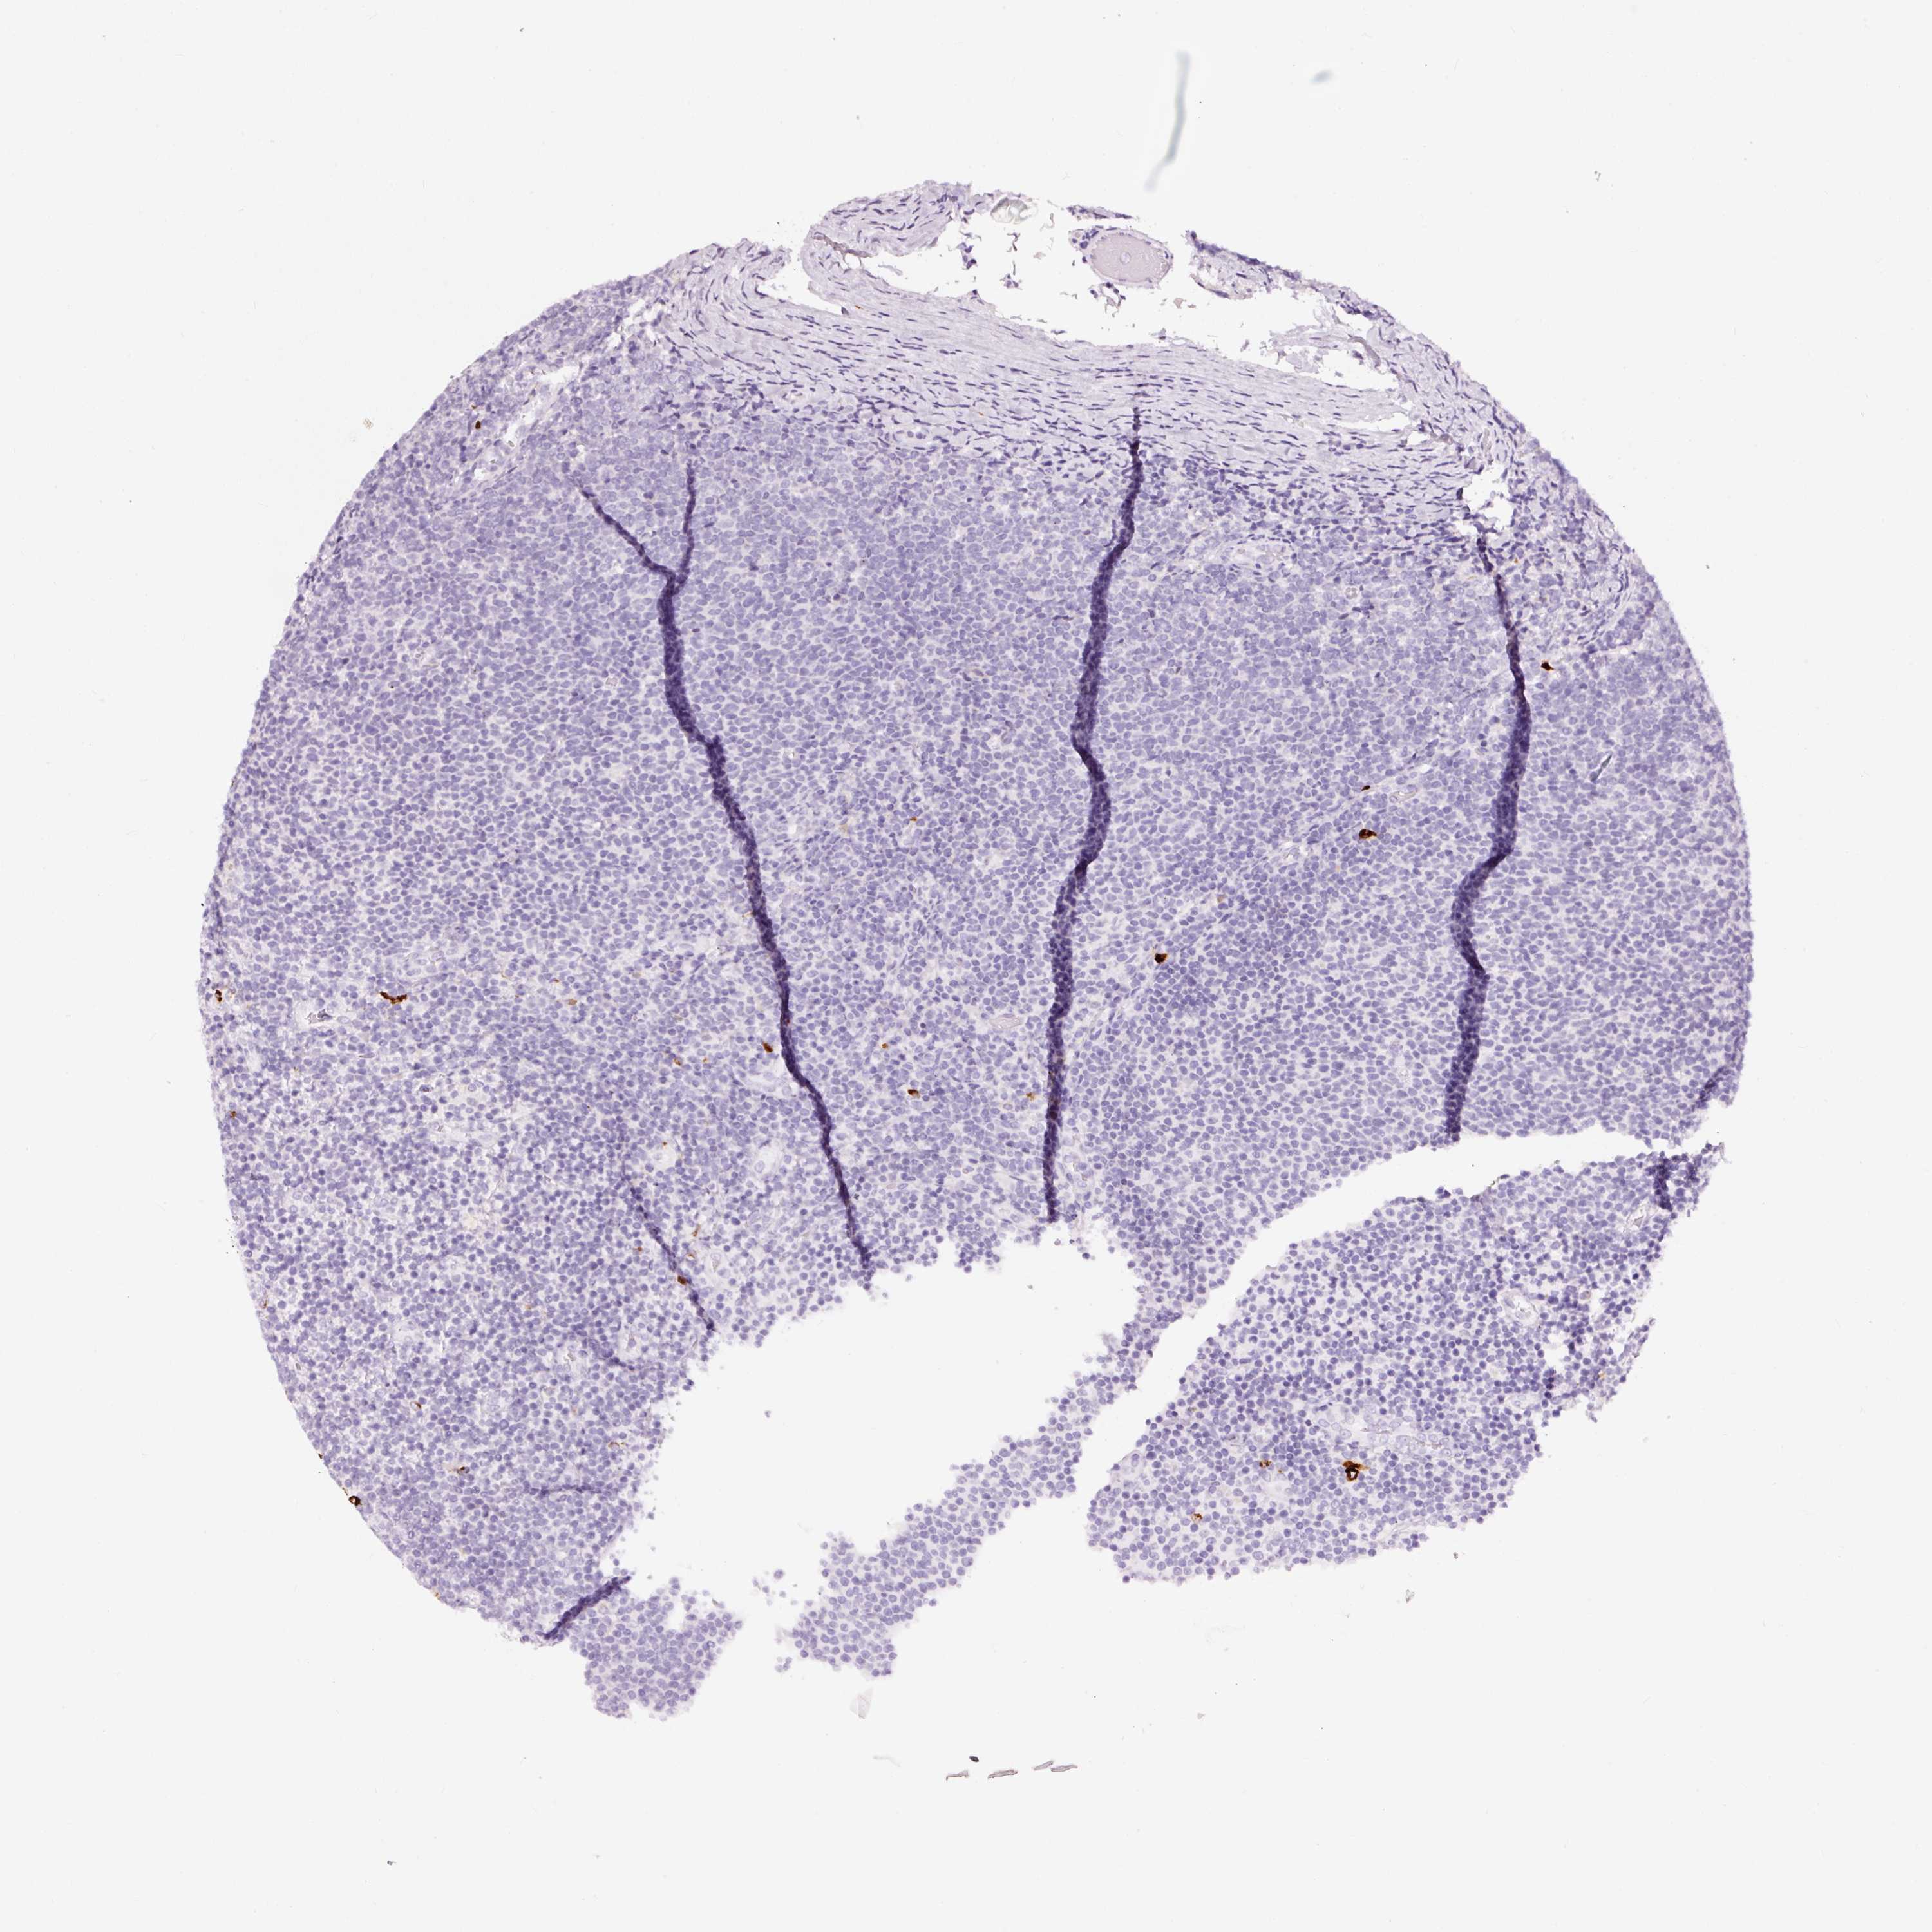

LYMPHOMA - Protein expressioni

A mouse-over function shows sample information and annotation data. Click on an image to view it in a full screen mode. Samples can be filtered based on level of antibody staining by selecting one or several of the following categories: high, medium, low and not detected. The assay and annotation is described here.

Antibody stainingi

Antibody staining in the annotated cell types in the current human tissue is reported as not detected, low, medium, or high, based on conventional immunohistochemistry profiling in selected tissues. This score is based on the combination of the staining intensity and fraction of stained cells.

Each image is clickable and will lead to virtual microscopy that enables deeper exploration of all samples and also displays staining intensity scores, fraction scores and subcellular localization as well as patient and tissue information for each sample.

Antibody HPA051467

Antibody CAB025133

Staining

High

Medium

Low

Not detected

Intensity

Strong

Moderate

Weak

Negative

Quantity

>75%

75%-25%

<25%

None

Location

Nuclear

Cytoplasmic/membranous

Cytoplasmic/membranous,nuclear

Hodgkin's disease, NOS

Malignant lymphoma, non-Hodgkin's type, High grade

Malignant lymphoma, non-Hodgkin's type, Low grade